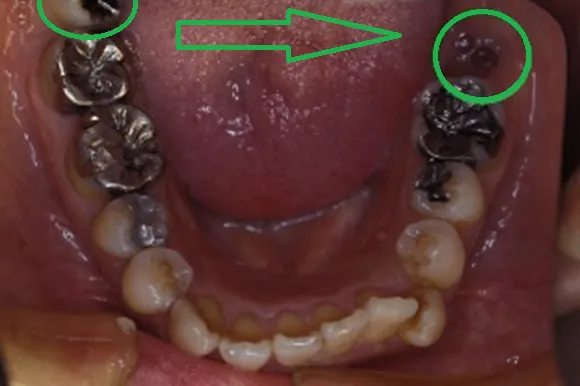

初診時

治療完了時

| 患者様のお悩み | 咀嚼障害(左下奥歯) |

| 治療法・使用素材 | 自家歯牙移植治療 |

| 患者様の年代 | 30代 |

| 治療開始年齢 | 30代 |

| 治療にかかった期間 | 6か月 |

| 性別 | 女性 |

| この治療のリスクについて | 移植歯が生着するかどうか |

| 治療にかかった費用 | 5万円 |